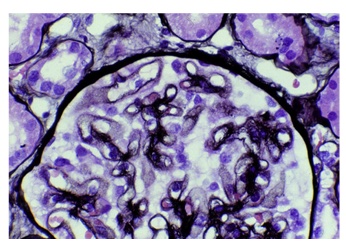

Light microscopy, immunofluorescence, and electron microscopy will reveal pattern of glomerular injury and severity.

[Figure caption and citation for the preceding image starts]: Mesangiocapillary glomerulonephritis showing (left) thickened capillary loops with diffuse cellular proliferation, giving characteristic 'lobular' appearance (light microscopy; stains: haematoxylin and eosin) and (right) coarse patchy granular immunofluorescent staining of IgM along capillary loopsFrom: Mason PD, Musey CD. BMJ. 1994 Dec 10;309(6968):1557-63 [Citation ends].